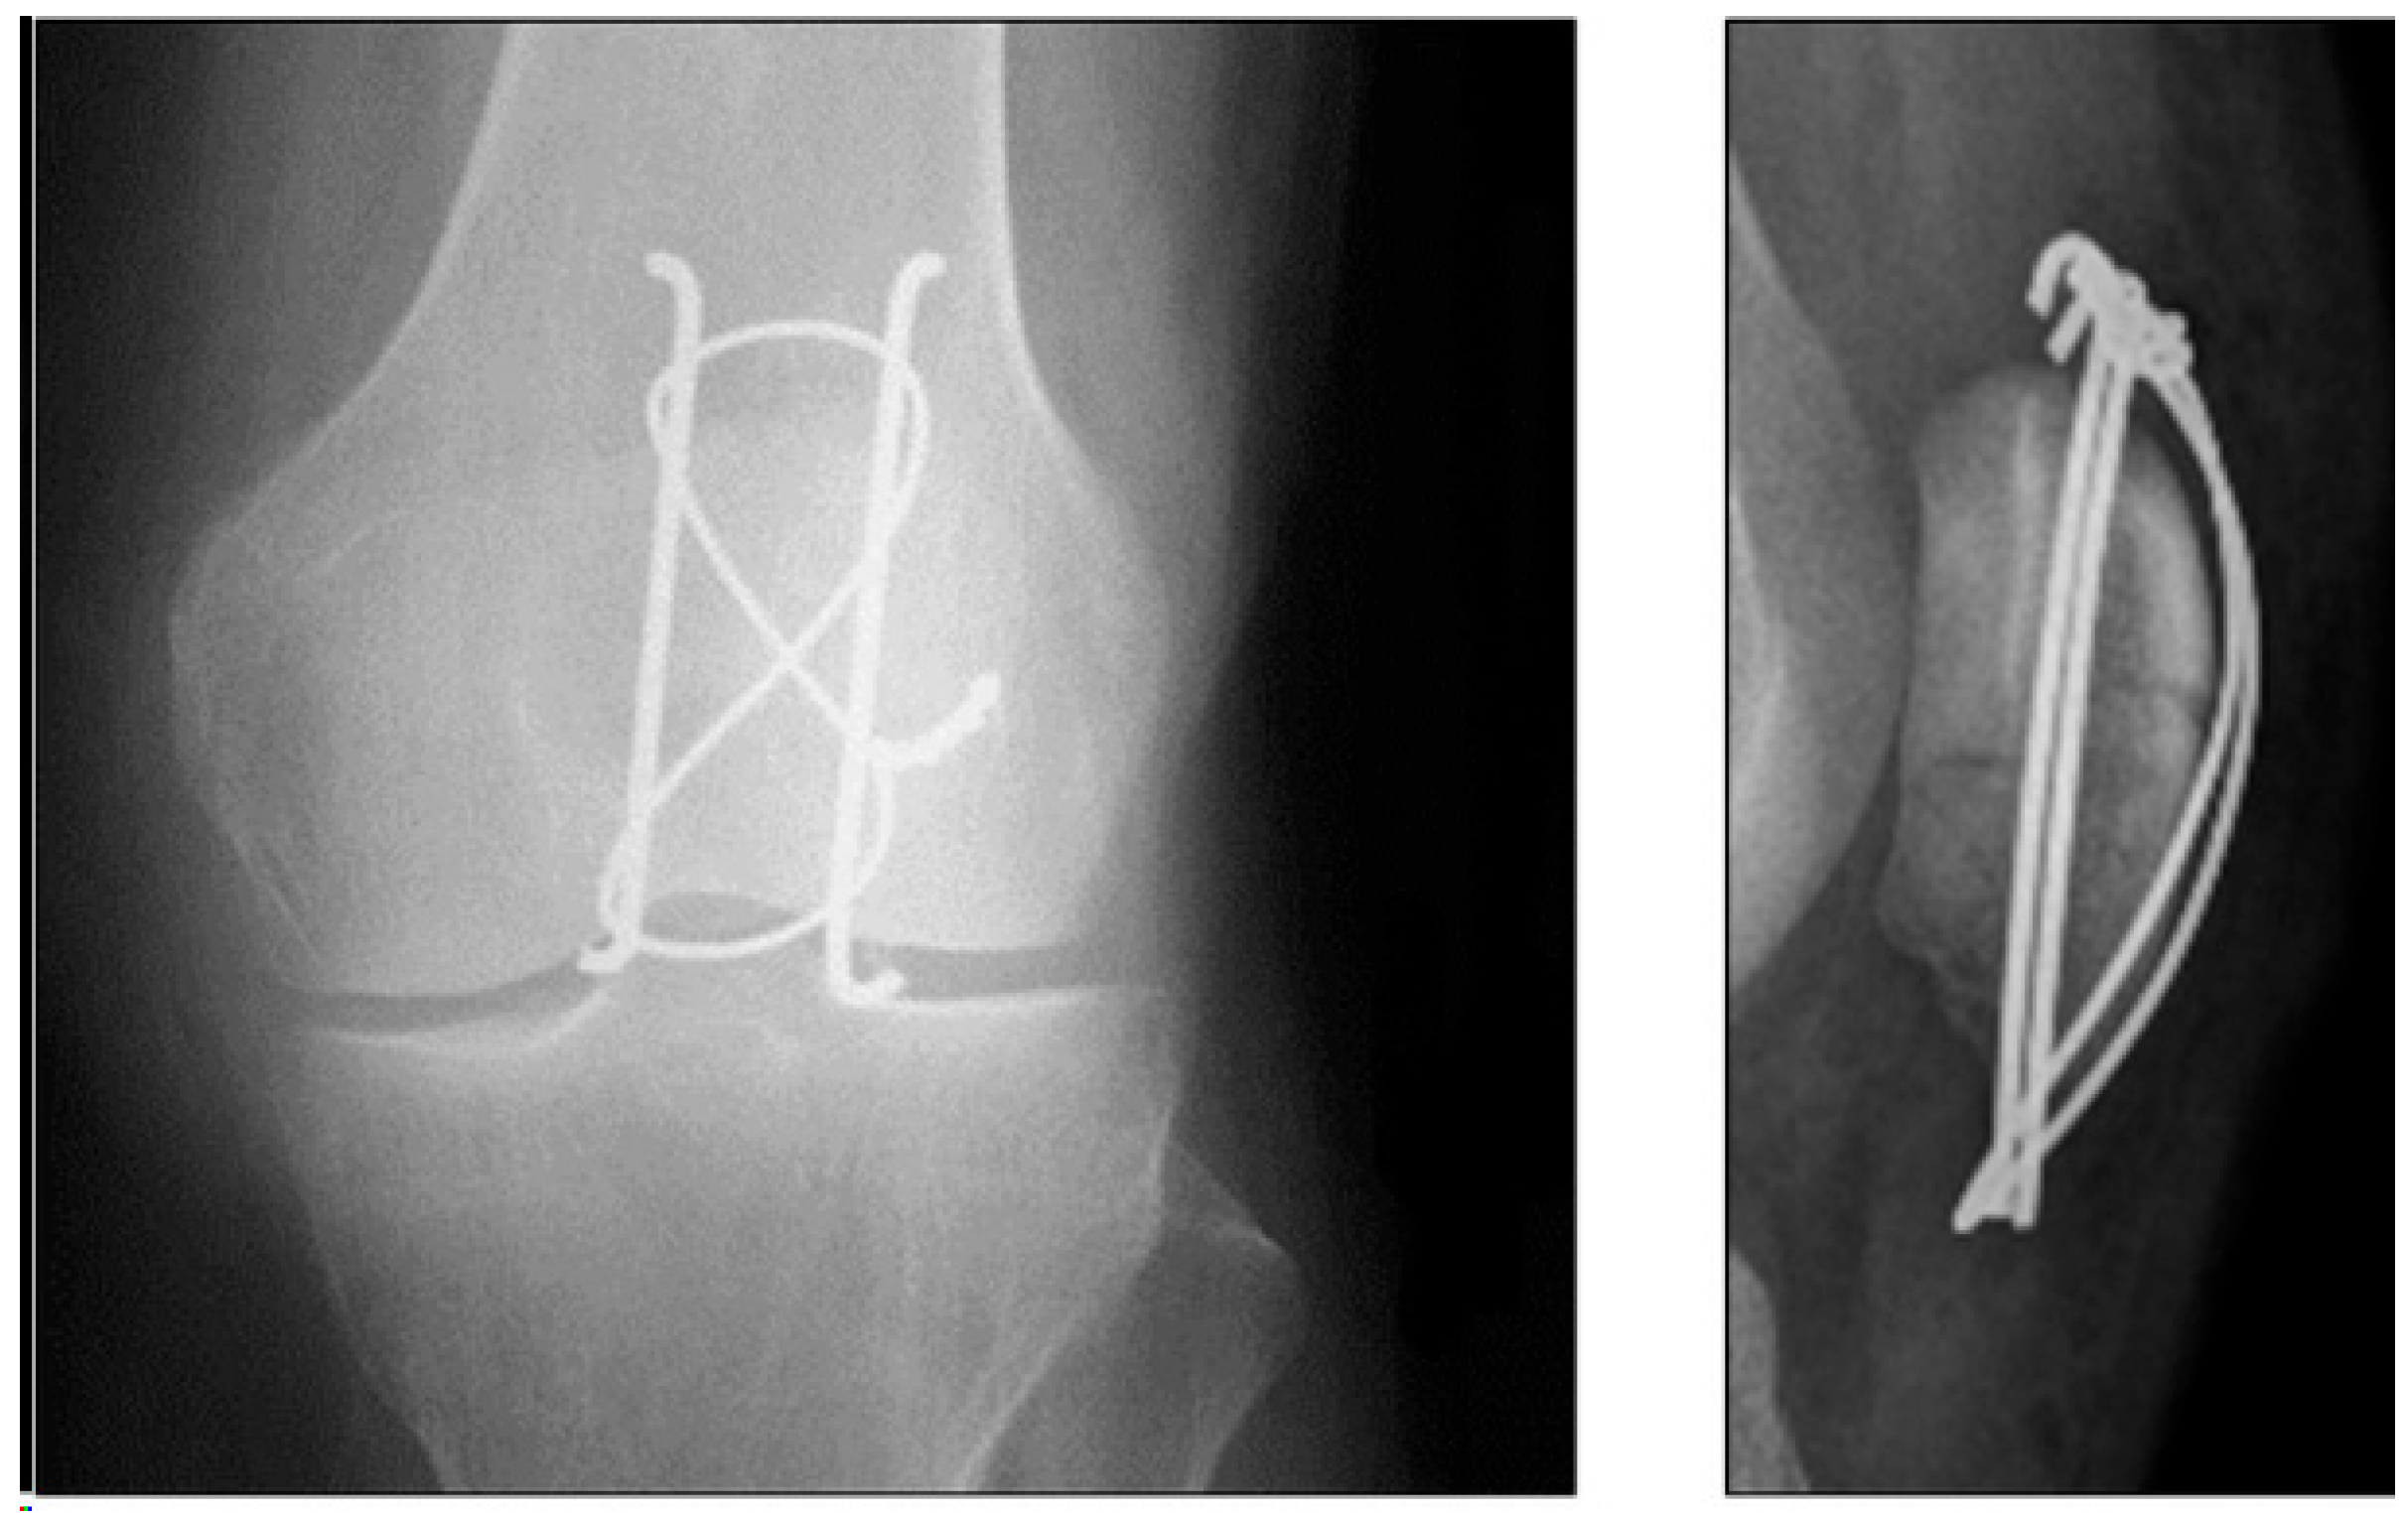

2.3. Tension Band Wire

- Benjamin, J.; Bried, J.; Dohm, M.; McMurtry, M. Biomechanical evaluation of various forms of fixation of transverse patellar fractures. J. Orthop. Trauma 1987, 1, 219–222. [Google Scholar] [CrossRef] [PubMed]

- Berg, E.E. Open reduction internal fixation of displaced transverse patella fractures with figure-eight wiring through parallel cannulated compression screws. J. Orthop. Trauma 1997, 11, 573–576. [Google Scholar] [CrossRef] [PubMed]

- Burvant, J.G.; Thomas, K.A.; Alexander, R.; Harris, M.B. Evaluation of methods of internal fixation of transverse patella fractures: A biomechanical study. J. Orthop. Trauma 1994, 8, 147–153. [Google Scholar] [CrossRef] [PubMed]

- Lotke, P.A.; Ecker, M.L. Transverse fractures of the patella. Clin. Orthop. Relat. Res. 1981, 158, 180–184. [Google Scholar] [CrossRef]

- Weber, M.J.; Janecki, C.J.; McLeod, P.; Nelson, C.L.; Thompson, J.A. Efficacy of various forms of fixation of transverse fractures of the patella. J. Bone Jt. Surg. Am. 1980, 62, 215–220. [Google Scholar] [CrossRef]

- Tian, Y.; Zhou, F.; Ji, H.; Zhang, Z.; Guo, Y. Cannulated screw and cable are superior to modified tension band in the treatment of transverse patella fractures. Clin. Orthop. Relat. Res. 2011, 469, 3429–3435. [Google Scholar] [CrossRef]

- Ha, C.; Sun, J.I. The treatment of patellar fracture with modified tension band wiring, using cannulated screws. J. Korean Fract. Soc. 2004, 17, 117. [Google Scholar] [CrossRef]